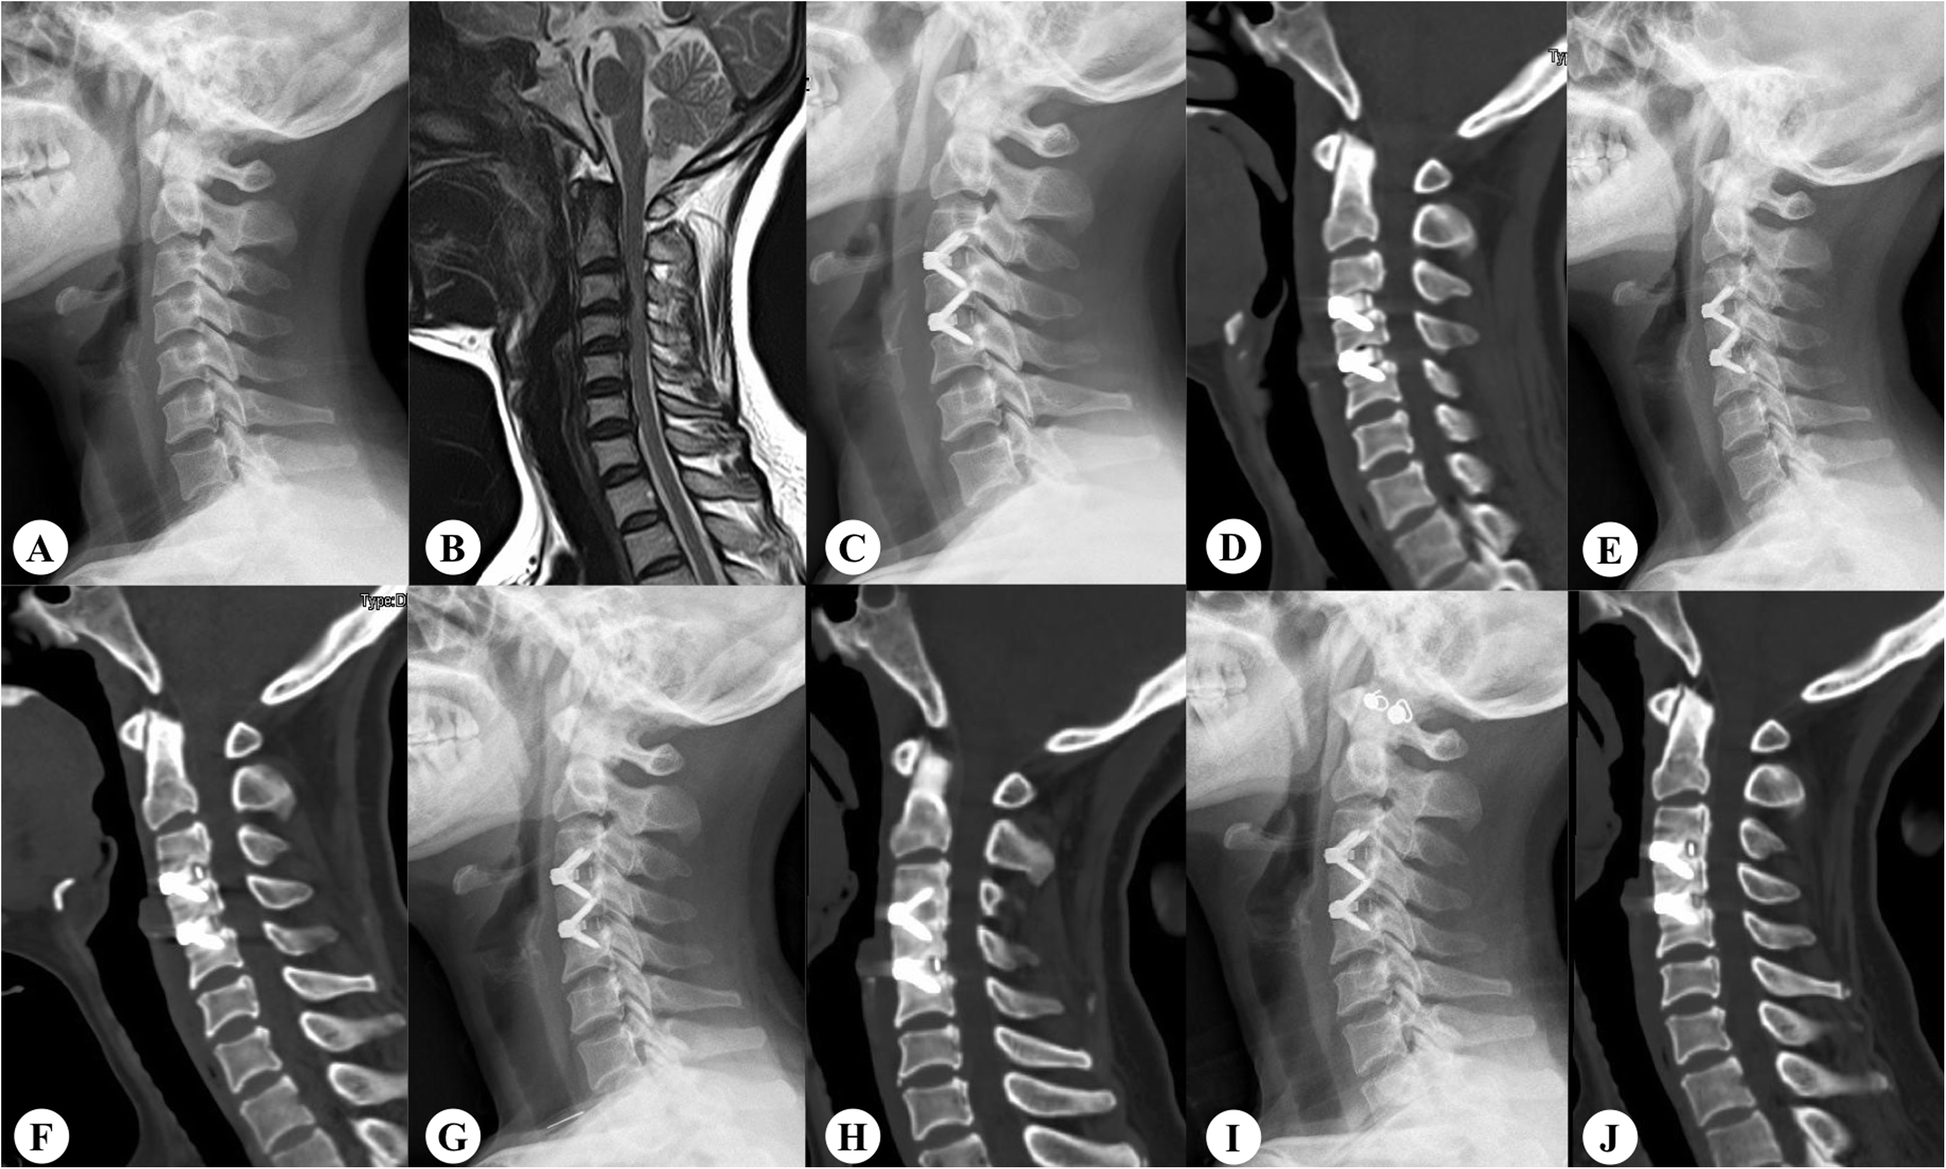

Fig. 2

Radiographs of a 49-year-old woman. A, B Preoperative lateral radiograph showing degeneration and compression at the C3/4 and C4/5 levels. C, D Postoperative image showing two suitable prostheses placed at those levels. E, F Three-month postoperative lateral radiograph showing a growing bridge only at the cranial level. G, H Fusion of only the cranial level at 6 months postoperatively. I, J At 2 years postoperatively, fusion of only the cranial level is complete